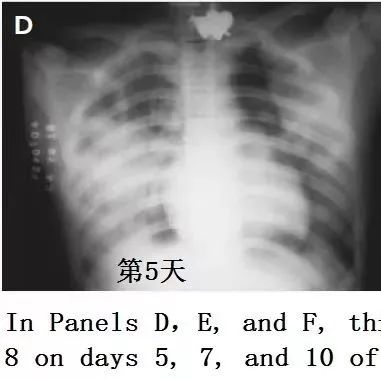

禽流感肺炎CT是啥样,不会诊断要出事! 医学界影像诊断与介入频道 · 公众号 · 医学 · 7 年前 · |